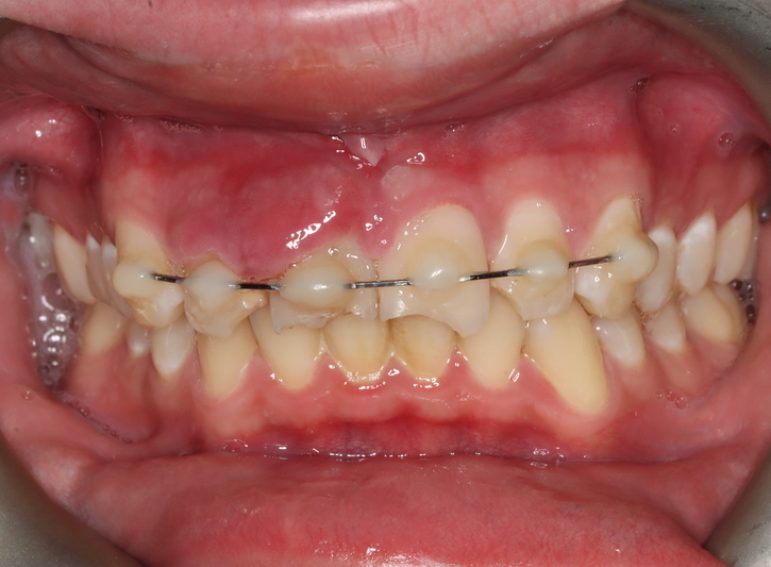

Surgical management of external cervical resorption.